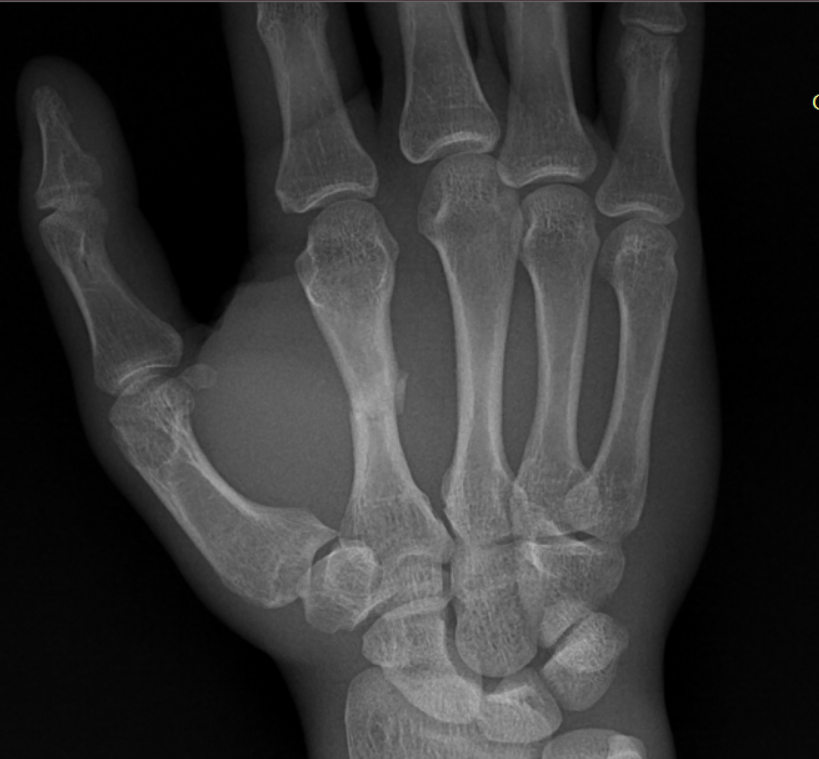

Переломы пястных костей диагностируются с клинического осмотра, во время которого врач оценивает симптомы и проводит физикальное обследование. Основным методом диагностики является рентгенография, которая позволяет визуализировать состояние костей и выявить наличие перелома. В некоторых случаях может потребоваться компьютерная томография (КТ) для более детального изучения повреждений, особенно если есть подозрение на сложные или нестандартные переломы.

Клинический случай: остеосинтез перелома 2 пястной кости — после операции

Контрольный этап: оценка ран, рентген-результаты и демонстрация восстановления движений после остеосинтеза.